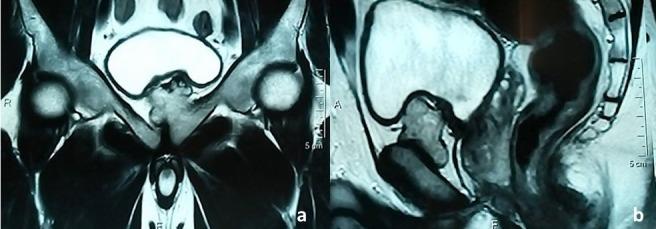

Osteochondroma is the most common benign bone tumor. It usually affects the metaphyses of the long bones, in particular around the knee and the proximal humerus. It very rarely affects the pubic symphysis, usually with an atypical symptomatology. We here report the case of a 35-year old man in whom osteochondroma in the pubic symphysis encroaching on the iliopubic branch was fortuitously discovered. Radiological examinations as well as macroscopic and histological examination confirmed the diagnosis and the absence of signs of malignancy.

骨软骨瘤是最常见的良性骨肿瘤。它通常影响长骨的干骺端,尤其是膝关节和肱骨近端周围。它极少影响耻骨联合,通常伴有非典型症状。我们在此报告一例35岁男性,其耻骨联合处的骨软骨瘤侵犯髂耻支,系偶然发现。影像学检查以及大体和组织学检查均证实了诊断且无恶性征象。